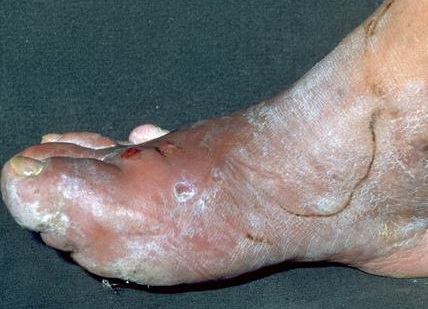

Foot infections are the most common problems in persons with diabetes. These individuals are predisposed to foot infections because of a compromised vascular supply secondary to diabetes. Local trauma and/or pressure (often in association with lack of sensation because of neuropathy), in addition to microvascular disease, may result in various diabetic foot infections. For additional information, see Medscape’s Diabetic Microvascular Complications Resource Center.

The spectrum of foot infections in diabetes ranges from simple superficial cellulitis to chronic osteomyelitis. Infections in patients with diabetes are difficult to treat because these patients have impaired microvascular circulation, which limits the access of phagocytic cells to the infected area and results in a poor concentration of antibiotics in the infected tissues. For this reason, cellulitis is the most easily treatable and reversible form of foot infections in patients with diabetes. Deep skin and soft tissue infections are also usually curable, but they can be life threatening and result in substantial long-term morbidity.

Diabetes mellitus is a disorder that primarily affects the microvascular circulation. In the extremities, microvascular disease due to “sugar-coated capillaries” limits the blood supply to the superficial and deep structures. Pressure due to ill-fitting shoes or trauma further compromises the local blood supply at the microvascular level, predisposing the patient to infection. The infection may involve the skin, soft tissues, bone, or all of these tissues.

Diabetes also accelerates macrovascular disease, which is evident clinically as accelerating atherosclerosis and/or peripheral vascular disease. Most diabetic foot infections occur in the setting of good dorsalis pedis pulses; this finding indicates that the primary problem in diabetic foot infections is microvascular compromise. Impaired microvascular circulation hinders white cell migration into the area of infection and limits the ability of antibiotics to reach the site of infection in an effective concentration. Diabetic neuropathy may be encountered in conjunction with vasculopathy. This may allow for incidental trauma that goes unrecognized (eg, blistering, penetrating foreign body).